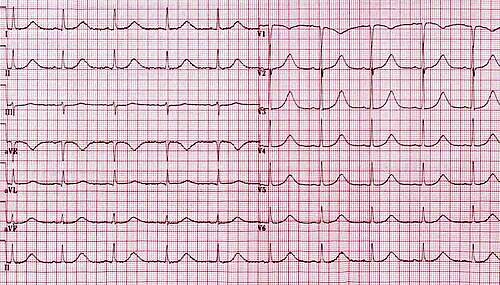

This ECG pattern is diagnostic of? A. Left bundle branch block B. Acute myocardial infarction C. Wolff-Parkinson-White (WPW) syndrome D. Hyperkalemia #NEETPG #MedTwitter Dr. Akhil 🇮🇳 Dr. Priyam Bordoloi Dr. Shiv_Kumar Antonio Arroyo, MD. Medico Cirujano. Dr. Medica🩺 MedLearn Hub Medzonetv

What is the first step in the management of a hemodynamically stable patient with the following rhythm shown on ECG? Options: A. IV Amiodarone B. Carotid massage C. Chest compressions D. Synchronized cardioversion #MedTwitter #Medx Dr. Akhil 🇮🇳 Dr. Priyam Bordoloi Dr. Shiv_Kumar